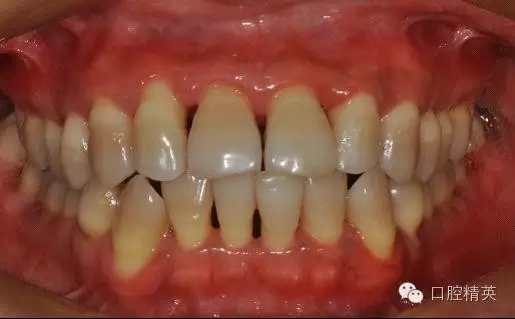

本病例 :女 34歲,主訴刷牙出血,覺牙齒輕度松動一年。

檢查見大量齦上及齦下結(jié)石,探診出血,牙周袋較深,32-42 II度松動。X線片顯示牙槽骨水平吸收。

治療前: